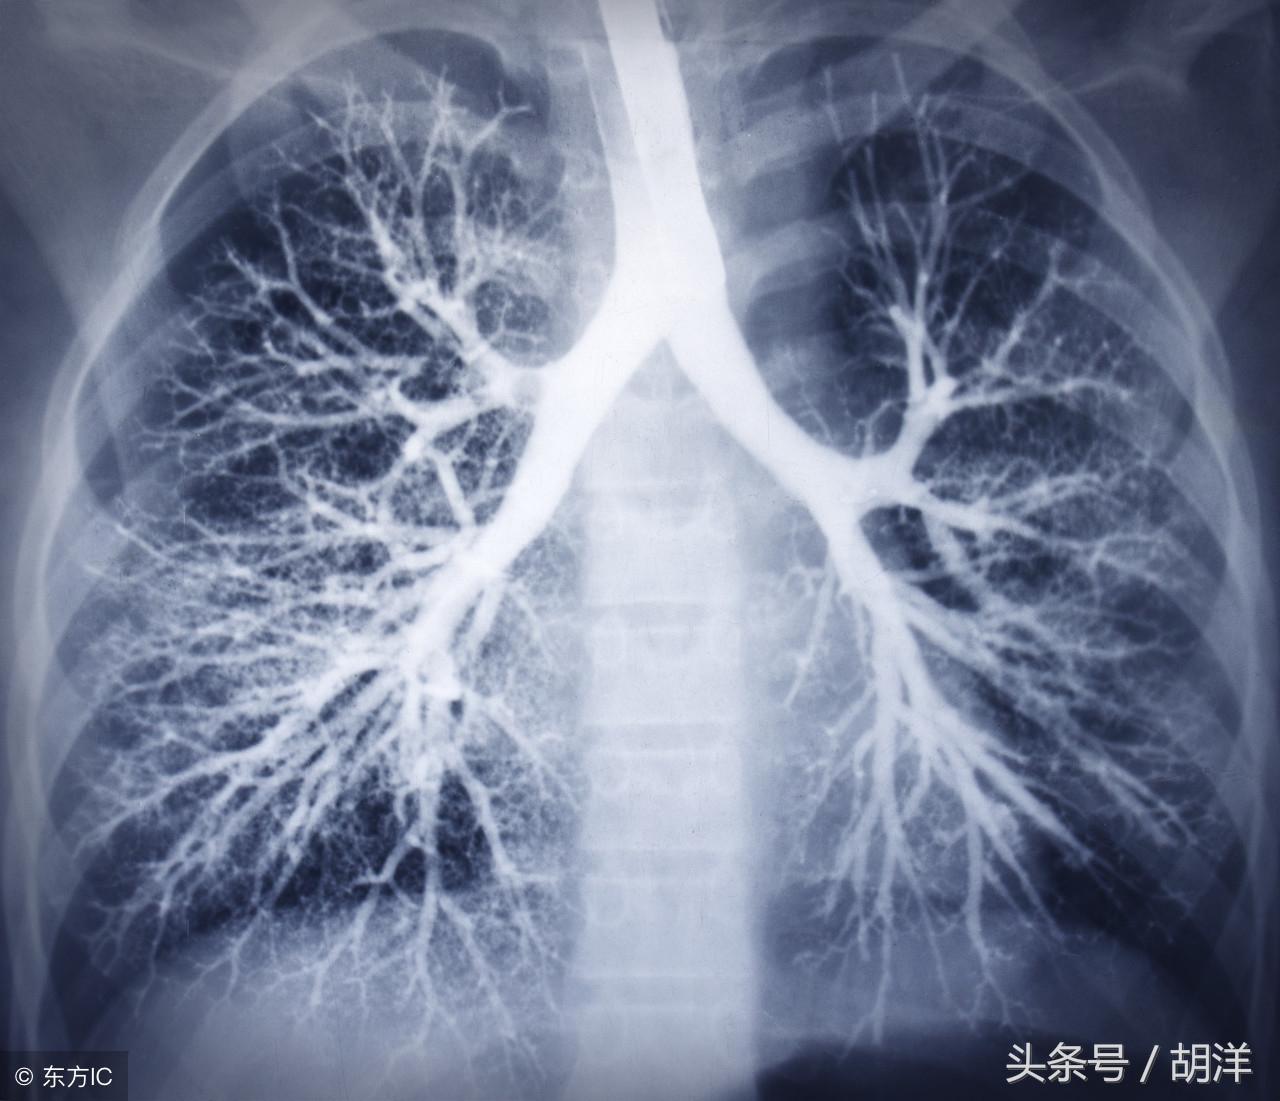

咳血又称咯血,是呼吸科一个比较严重的症状,由于其可能提示肺部肿瘤等严重疾病而受到重视,但事实上在引起咯血的病因中,肺部恶性肿瘤所占的比例并不是很大,但很多人因咯血而焦虑异常,特别是咯血久治不愈情况下,更加令人无法正常的生活和学习,那么哪些疾病可能导致反复发作痰中带血或者咳出满口鲜血呢?

支气管扩张

支气管扩张是一种支气管管壁结构破坏性疾病,正常情况下,支气管是一个带有弹性,拥有一定管径的能够维持正常呼吸通气的结构,当管壁结构受到破坏时,气管会受到被动的牵拉而扩张,管壁的血管由于弹性较小,容易被撕扯呈血管瘤改变,一旦胸腔内血流压力增大可能冲破血管瘤变薄的管壁而导致大咯血,少量渗血时则呈现为痰中带血。

肺结核

肺结核是一种肺部传染性疾病,是由于结核菌在肺部生长并破坏肺部结构导致的,对于肺部的损害很大,寄生的肺组织局部甚至会完全毁损形成干酪样坏死物排出体外,这样的破坏难免侵蚀血管导致出血,也是大咯血的原因之一。